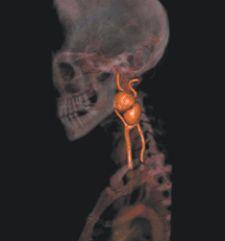

Significant advances have also been achieved in segmentation technologies, which allow clinicians to remove extraneous anatomy during review, but one of the more difficult segmentation challenges is separating small arteries from bone – for example, the deep palmar arch – and isolating this artery using traditional 3-D workstation software tools.

Barco just received FDA 510(k) clearance for CardiaMetrix, its clinical application suite for structural and functional analysis of contrast-enhanced cardiac studies. Integrated into PACS with Voxar 3D and VesselMetrix, a clinical application for quantitative vessel analysis of CTA and MRA, CardiaMetrix’s segmentation and bone removal software is designed to allow users to extract small vessels quickly and provides a 4-D cardiac analysis tool to produce 4-D movies of the beating heart with cardiac contours. The 4-D cine rapidly generates short axis, two-, three- and four-chamber long axis views, semi-automatic alignment with cardiac long axis position and automatic transfer of long axis position in end-diastolic and systolic phases to cardiac (LV) analysis.